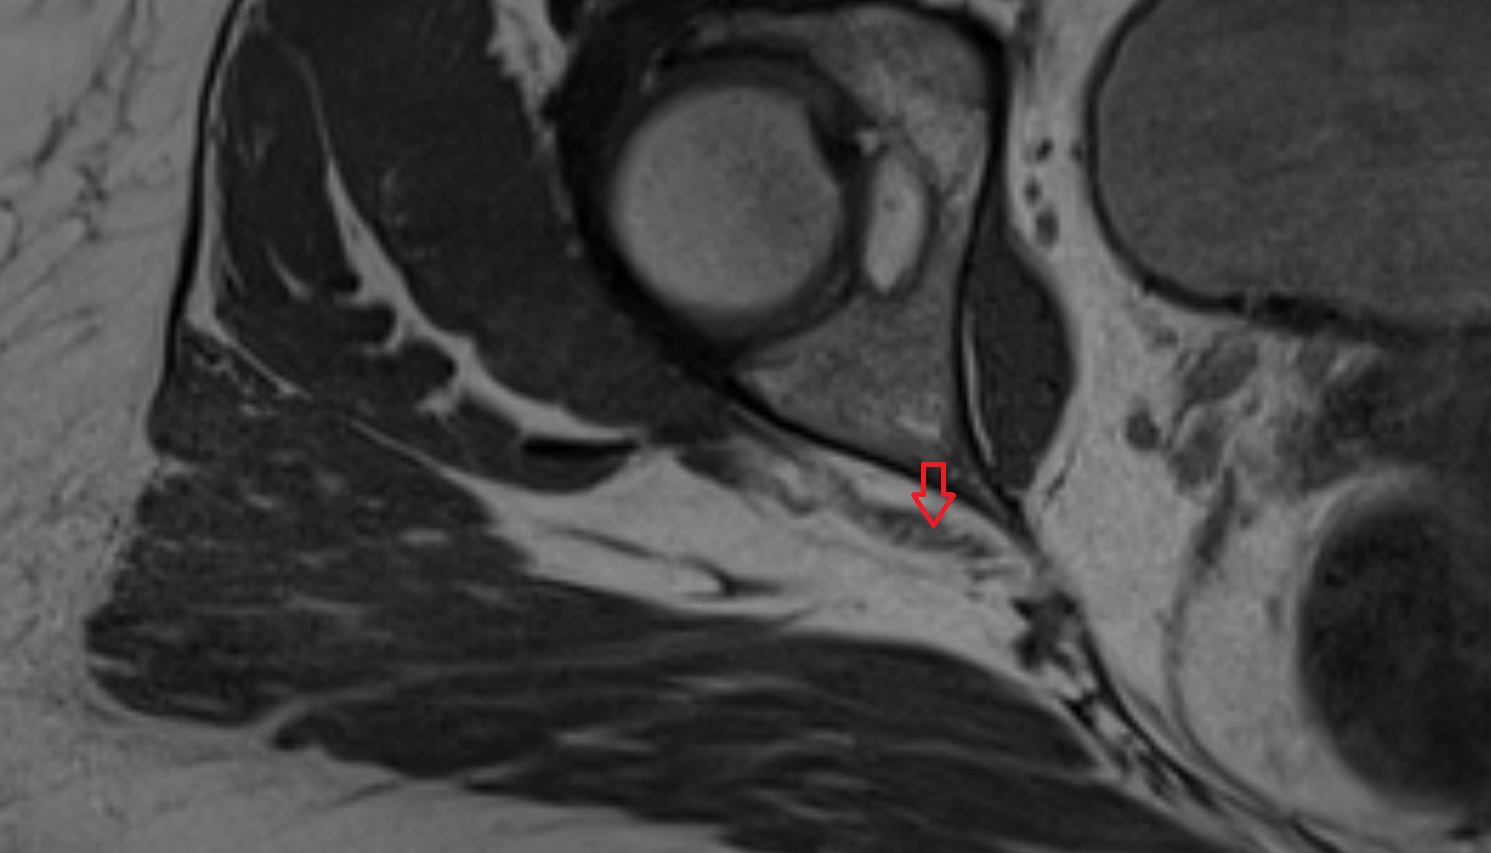

- Hip joint